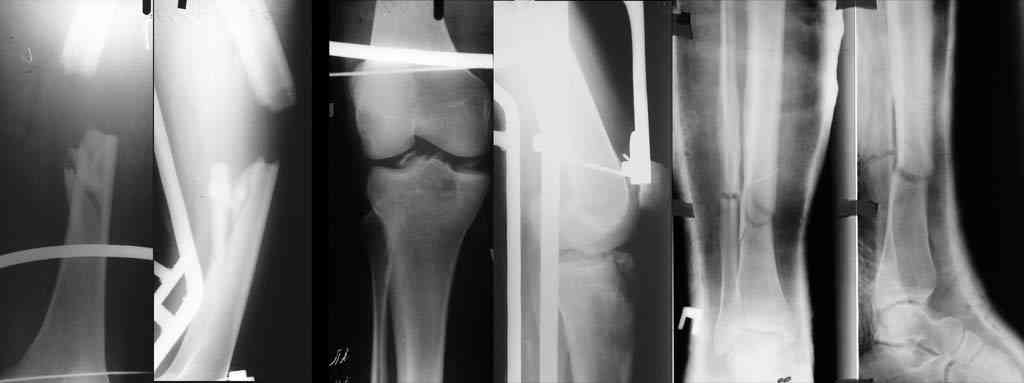

К нам переведен больной 36 лет (175 см рост, 105 кг масса тела), который 64 дня назад в ДТП получил множественную скелетную травму: перелом вертлужной впадины справа с задним вывихом бедра и повреждением крестцово-подвздошного сочленения справа, оскольчатым (тип C3) переломом диафиза правого бедра на границе с/3 - н/3, открытый (тип III В по Каплану-Марковой) краевой перелом мыщелков правой большеберцовой кости, закрытый поперечный перелом диафизов костей правой голени на границе с/3-н/3 (т.е. все повреждения справа). Судя по анамнезу, имело место сдавление правой голени и бедра около 1,5 часов. В ЦРБ (по месту получения травмы) был доставлен в тяжёлом травматическом шоке, отмечались признаки ОПН (в частности, олигурия и подъём уровня креатинина выше 300 ммоль/л). Судя по анамнезу, более месяца сохранялся резко выраженный отёк правого бедра. Из выписки известно, что безуспешные попытки закрытой репозиции вывиха бедра были выполнены при поступлении в ЦРБ. Больному также выполнен накостный остеосинтез диафиза правого бедра. Рана зажила первичным натяжением. Голень фиксирована гипсовой повязкой. В области правого коленного сустава остаётся обширная рваная рана с дефектом кожи (до 20x20 см), частично закрытая дерматомными лоскутами, из которой высевается полирезистентный acinetobacter. Продолжает эпизодически лихорадить (до 38), сохраняется лейкоцитоз (11-14 тыс), в ряде анализов крови отмечался сдвиг до миелоцитов (1-6%). В остальном - без видимой патологии. Отёк бедра в настоящее время незначительный. После перевода наложено вытяжение за бедро 12 кг. Хотелось бы узнать мнения о вариантах тактики лечения перелома вертлужной впадины и вывиха бедра (учитывающие и давность травмы, и сопутствующие повреждения). Хотя этот нюанс совсем немедицинский, но замечу, что больной не настроен на любые виды платной медицинской помощи. Имеющиеся рентгенограммы и КТ приложены. С уважением Игорь

К сожалению, отправить все снимки и КТ сразу не получилось. Дополняю.

Действительно, картинка с пластинкой делает сращение вообще сомнительным, так что эндопротезирование может отложиться на неопределенный срок. Надежнее пластинку из бедра убрать малонвазивно, и закрыто бедро заштифтовать.

Надо прикинуть, может быть перелом настолько низкий, что с недлинным ретроградным стержнем останется достаточно места для ножки протеза. И можно будет сделать первичное протезирование из положения как есть сейчас.

Я за агрессивную тактику- молодой пациент с поперечным трансвертлужным переломом таза,перелом задней стенки впадины с вывихом бедра+наружная ротация проксимального отломка таза с повреждением lig.sacroiliac interosseous anterior.Конечность в наружной ротации,как нерв?

Учитывая перелом задней стенки верл.впадины из доступа Кохера-Лангенбека репозиция-фиксация таза-вправление вывиха-синтез впадины.Фиксация таза на уровне передней и задней колонн во избежании ротационных смещений.Удаление пластины и реостеосинтез бл.штифтом-согласен.

Скорее всего перелом Т-образный и головка вроде бы цела. Я бы разобрал впадину и собрал обратно с фиксацией трансфрактурными винтами передней колонны и мостовидной пластинкой задней. Перед открытой реконструкцией возможно наложил бы аппарат таз бедро для низведения головки, если пластина на бедре выглядит надежной.